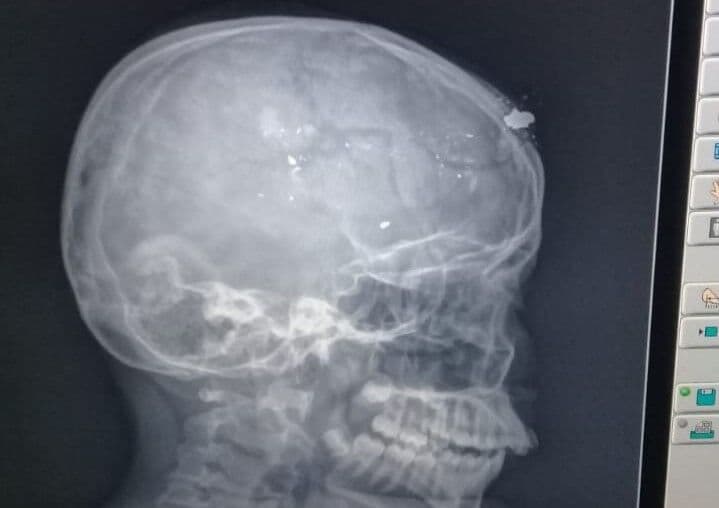

Criança atingida com tiro na cabeça em Catolé do Rocha teve fratura e afundamento do crânio